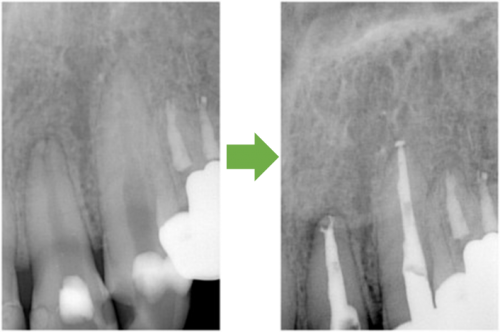

抜髄 右上の小臼歯 川口の歯科 歯医者 さかえ歯科クリニック

2014年12月17日